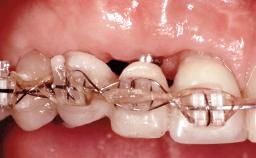

Replacement of Four Incisors with a Fixed Partial Denture on Two Narrow-Neck Implants after Implant Failure

| Type of Implants | One-Piece|Reduced-Diameter |

| Prosthesis Type | FDP |